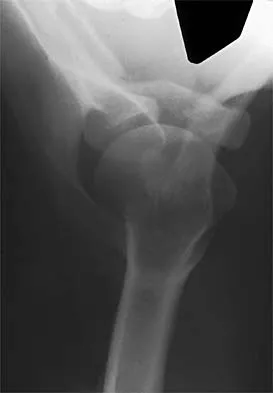

Figure 31 shows the AP and lateral radiographs of the elbow of a 56-year-old man with chronic polyarticular rheumatoid arthritis. His function continues to be limited by pain with activities of daily living. Examination shows that his total arc of motion is 110 degrees. Nonsurgical management has failed to provide relief. Treatment should now consist of

A semiconstrained prosthesis can provide excellent results in carefully selected patients. Because the radiographs show extensive joint destruction with loss of the capitellum and trochlea, a capitellocondylar total elbow (unconstrained) prosthesis is contraindicated. Elbow fusion is poorly accepted, and the radiographs show too much articular destruction for a radial head excision, synovectomy, or interposition arthroplasty to be effective. Ewald FC, Simmons ED Jr, Sullivan JA, et al: Capitellocondylar total elbow replacement in rheumatoid arthritis: Long-term results. J Bone Joint Surg Am 1993;75:498-507.